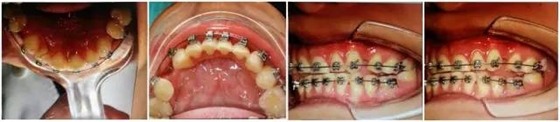

以上群里多位醫(yī)生的探討基本與權(quán)老師的處理方案接近。權(quán)老師的最終治療是通過樹脂暫時恢復(fù)尖牙引導(dǎo)功能,側(cè)方引導(dǎo),使上下前牙分離了,緩解前牙創(chuàng)傷;做完舌側(cè)的功能恢復(fù),后牙打開較多,在某種程度上對后牙也有很大保護(hù)。

(以下為治療后的照片:患者癥狀得到了良好改善。)

足以看出,尖牙保護(hù)(牙合)在臨床工作中的重要作用,它是以尖牙為支撐,對其他牙齒起到保護(hù)作用。其特點(diǎn)是正中關(guān)系(牙合)與正中(牙合)協(xié)調(diào);側(cè)方咬合運(yùn)動時,工作側(cè)只有尖牙保持接觸非工作側(cè)牙齒不接觸;在作前伸咬合運(yùn)動時,上下頜前牙切緣相對接觸,后牙不接觸。尖牙具有適合制導(dǎo)的舌面形態(tài),可使用(牙合)力趨于軸向;牙根長且粗大,支持力強(qiáng);尖牙位居牙弓前部,在咀嚼時構(gòu)成第Ⅲ類杠桿,能抵御較大的咀嚼力;以及尖牙牙周膜感受器豐富,對刺激敏感,能及時調(diào)整反應(yīng)都是尖牙的有利條件。尖牙形態(tài)的恢復(fù)在此例正畸治療中,對前牙、后牙都起到了很好的保護(hù)作用,也能保證后期按照標(biāo)準(zhǔn)(牙合)進(jìn)行(牙合)重建時后牙無干擾。功能在先,美觀在后,權(quán)老師為您展示了這樣的治療理念。